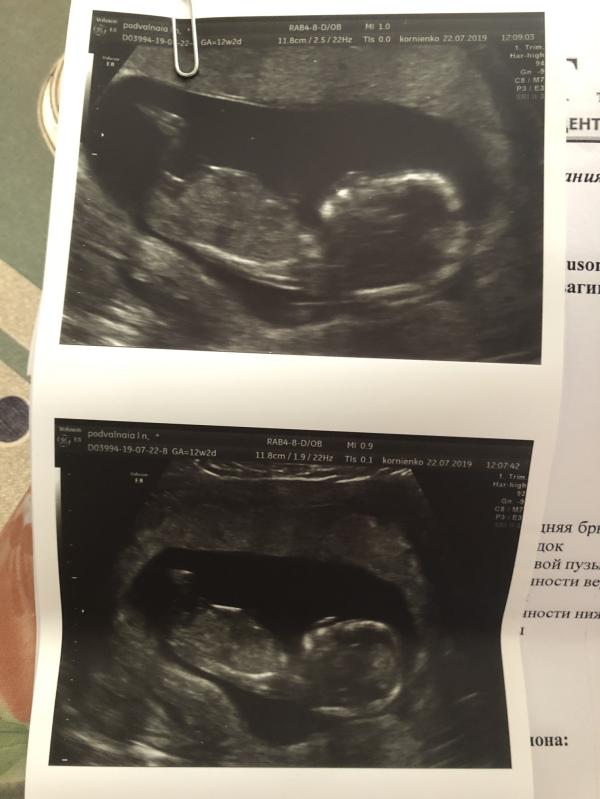

Первый скрининг пройден, всё хорошо, у нас мальчик

УЗИ сразу, кровь в понедельник сдала в пятницу будет готова